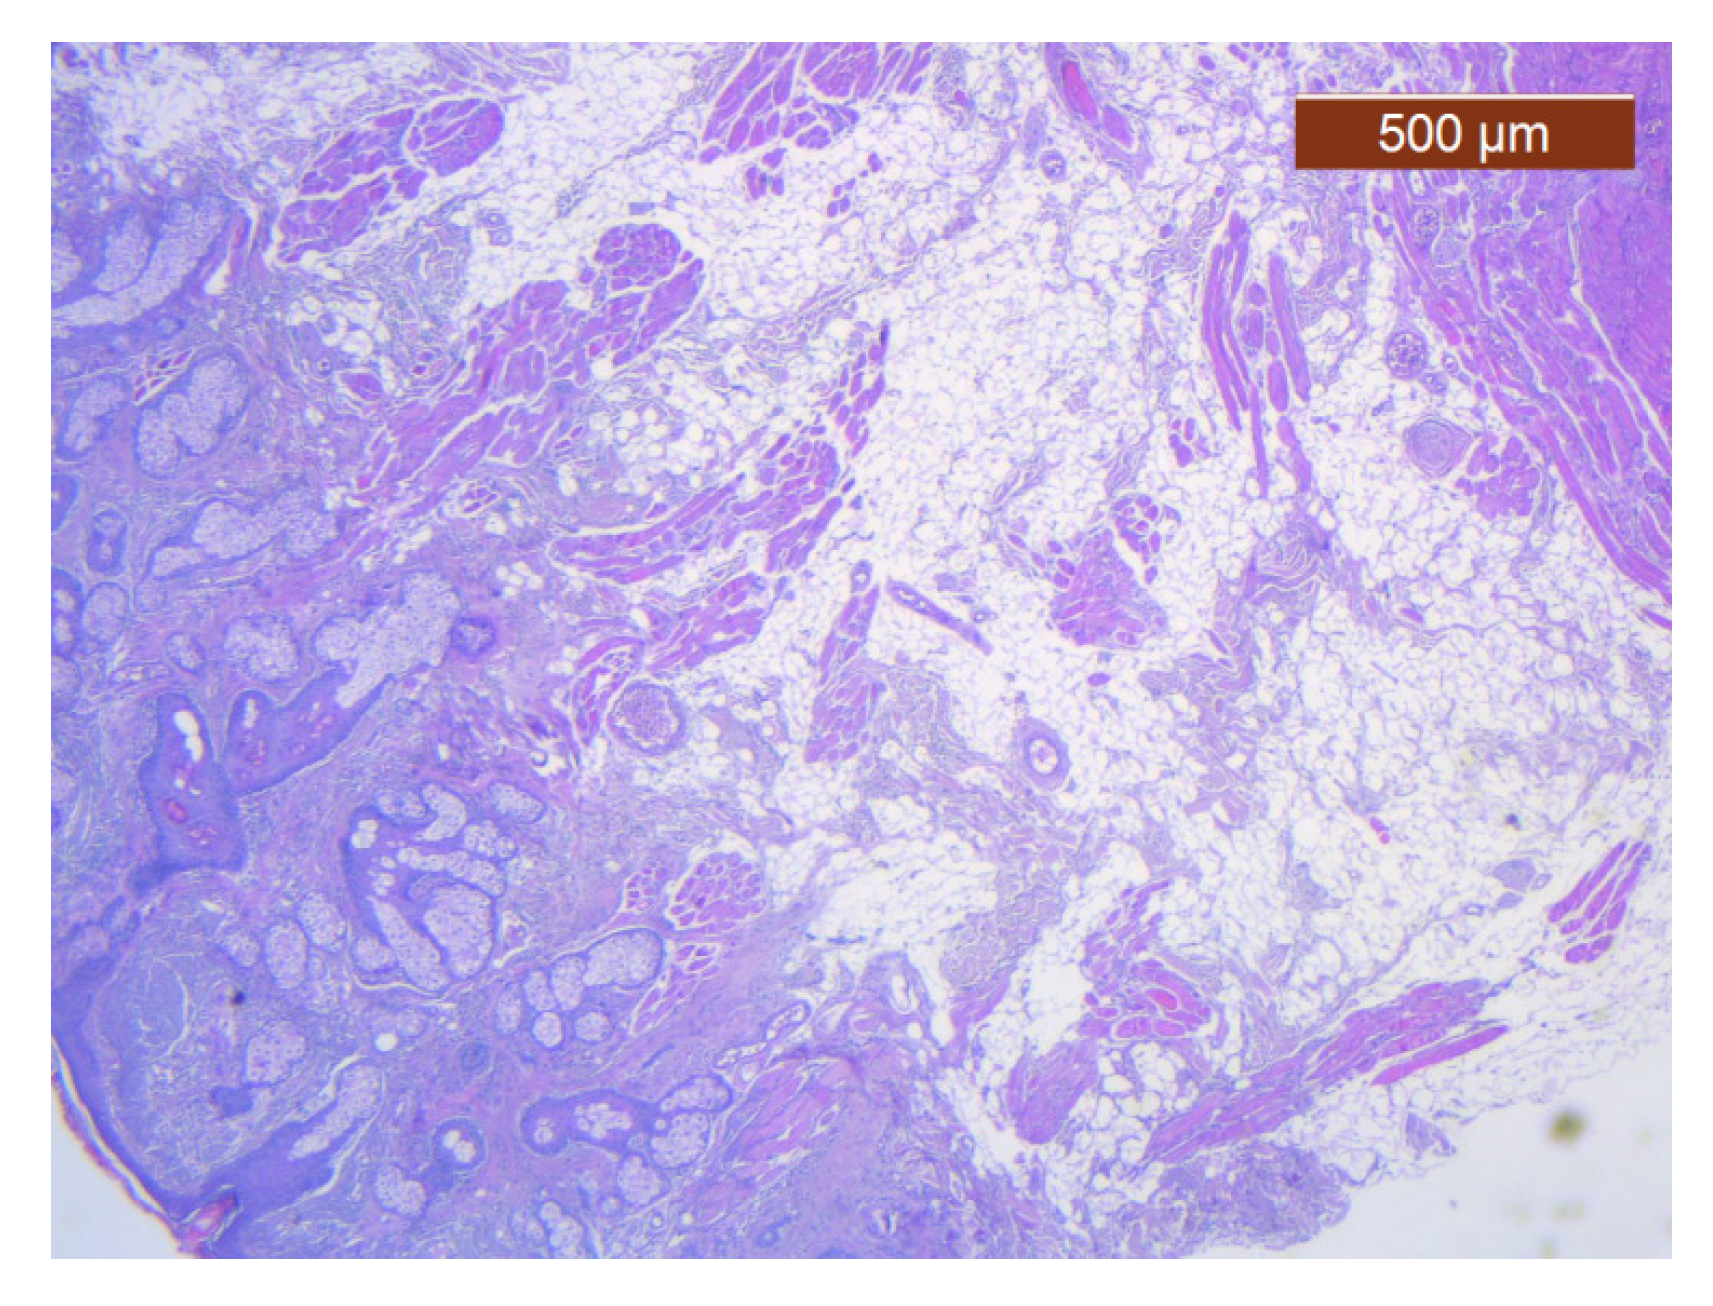

Figure 24. General histological view that showed the depth of the SMAS from the surface of the skin (HE ×2.5). Histological piece from biopsy of the lower lip.

Figure 23. Fibroadipose tissue over the SMAS, well represented with the average thickness of the soft tissue structure (HE ×2.5). Histological piece from biopsy of the lower lip.

Through the usual staining, a very well-represented layer of collagen can be observed at the levels of both lips (Figure 23 and Figure 24).

Muscle fibers are also visible and take direct cutaneous insertion, perpendicular to the skin, crossing the superficial fascia (Figure 25 and Figure 26).